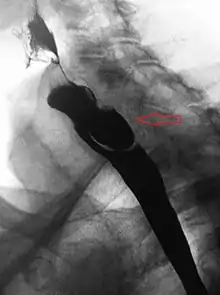

A Zenker's diverticulum, also pharyngeal pouch, is a diverticulum of the mucosa of the human pharynx, just above the cricopharyngeal muscle (i.e. above the upper sphincter of the esophagus). It is a pseudo diverticulum or false diverticulum (only involving the mucosa and submucosa of the esophageal wall, not the adventitia), also known as a pulsion diverticulum.

When there is excessive pressure within the lower pharynx, the weakest portion of the pharyngeal wall balloons out, forming a diverticulum which may reach several centimetres in diameter.

While traction and pulsion mechanisms have long been deemed the main factors promoting development of a Zenker's diverticulum, current consensus considers occlusive mechanisms to be most important: uncoordinated swallowing, impaired relaxation and spasm of the cricopharyngeus muscle lead to an increase in pressure within the distal pharynx, so that its wall herniates through the point of least resistance (known as Killian's triangle, located superior to the cricopharyngeus muscle and inferior to the thyropharyngeus muscle. Thyropharyngeus and cricopharyngeus are the superior and inferior parts of inferior constrictor muscle of pharynx respectively). The result is an outpouching of the posterior pharyngeal wall, just above the esophagus.[3]

A combination of the simple barium swallow and a thorough endoscopy will normally confirm the diverticulum.[4]